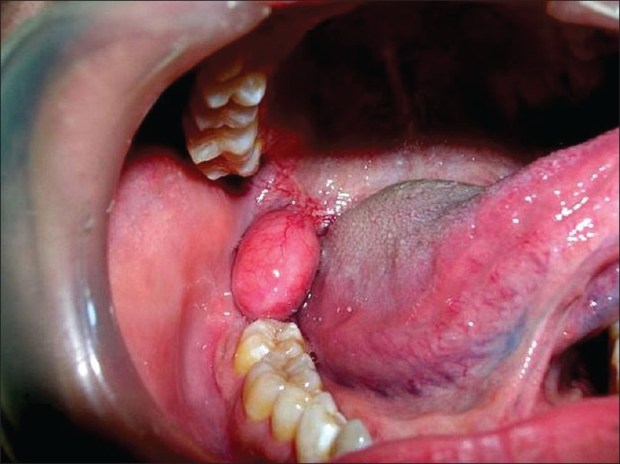

1-s2.0-S1991790213000792-gr1

Unknown

Unknown-1

Multicystic ameloblastoma can infiltrate into the adjacent tissue and has the ability to recur and even metastasize:

• Its prevalence is a slightly older age group than the unicystic ameloblastoma.

• Radiographically, the appearance is generally unilocular or multilocular.